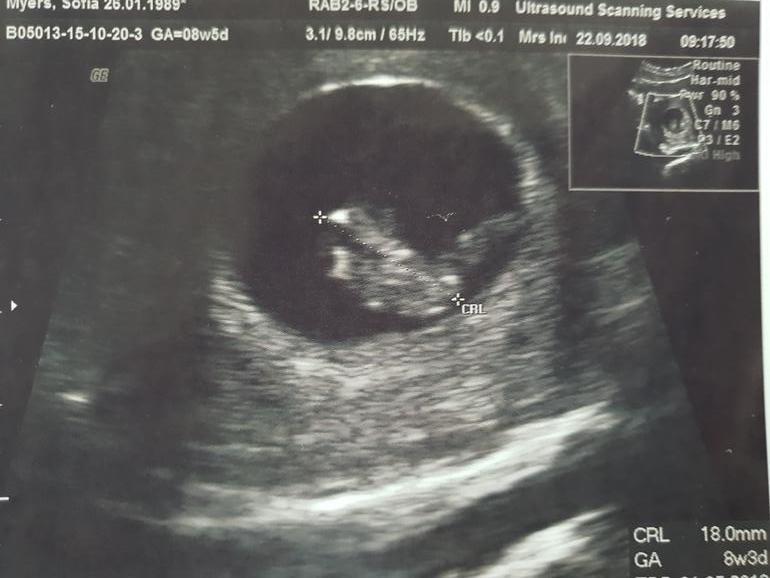

Узи в 8.5 :)

На узи были все вместе, все нашли посмотрели и послушали сердечко, 173уд/м. Но высоко матка, прям уже на уровне чуть ниже пупка, конечно живот будет уже виден. Связки не те, мышцы расслаьились, пресс вообще не могу подключать и Слава богу. Мне дальнейший разрыв грыжи не нужен.

Размер мне поставили даже больше, чем по М, хотя и поздняя гестация была. 8 нед 5 дней.

Все в норме, можно работать дальше и идти в 10ю неделю спокойно.